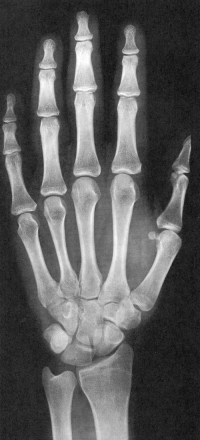

Sexo Masculino

7 anos

8 anos